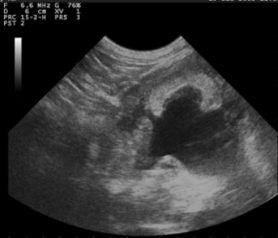

羊用B超机对双顶径(BPD)的测定

BPD的超声测量是常规的在产前检查和估计期间进行各种山羊品种中的GA含量,测量的标准BPD如下:尽可能椭圆形,封闭头骨表轮廓,大脑中线分裂克将半球分成两个等距的部分并测量-取自近端的外表面颅骨到远端颅骨内表面。头部扫描应在轴向平面上进行。图像对称性对于准确测量至关重要。很高相关性之间妊娠中期GA和BPD已经升高,BPD是也很难之后测量胎儿出生后第95天胎儿其他部位压迫头部,和也的变化性的胎儿的位置和姿势。因此,据报道,相关系数较低第60至135天之间的韩国黑山羊妊娠。

图3超声检查图片的双顶直径上胎儿在妊娠40天

图4超声图像上的双顶径胎儿在妊娠70天